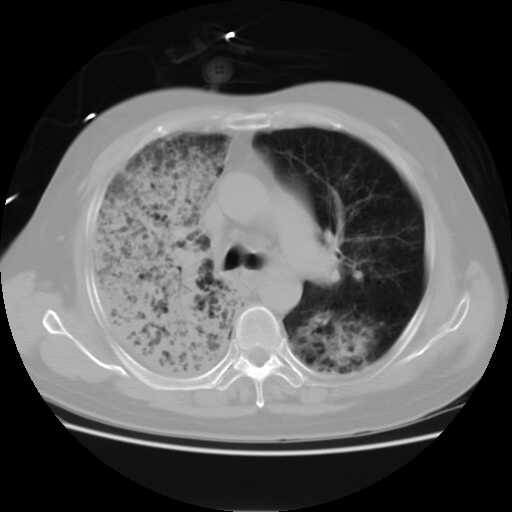

2008.8.17ct

病变从8.11-8.17明显改变,增多,以蜂窝状改变为主,类蜂窝肺,似弥漫性肺泡癌,但是病变进展太快,不符合弥漫性细支气管肺泡癌。因此考虑为特殊微生物感染,多以霉菌类常见,建议细菌微生物学检查。

疑点二:影象表现怪异,大片阴影内见多发筛孔征,如何解释.

结合临床慢支炎肺气肿,肺心病病史,三次胸片观察可见病情发展变化迅速,病情凶险,考虑多重感染伴ards.